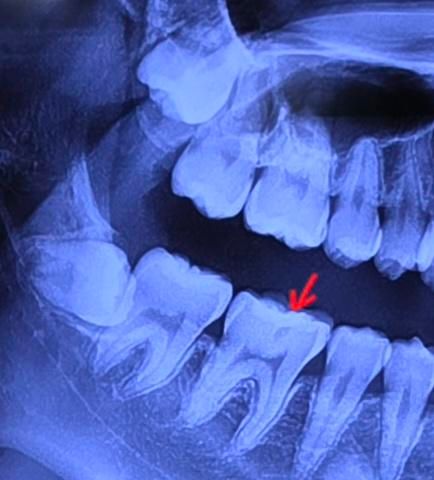

1. 사랑니: 다 매복입니다ㅠ 근데 아래 오른쪽 사랑니(사진 상 왼쪽)가 옆이빨이랑 겹쳐서 저렇게 나타난 건가요? 아님 썩거나 염증때문에 옆 부분이 하얗게 보이는 건가요?

2. 빨간색 화살표한 부분에 안쪽이 충치인가요? 겉에서부터 썩은게 아니라 안쪽에서 썩어서 저렇게 보이는건가요?

• 1번 째 사진

파노라마 사진은 입체를 2d로 표현하기 때문에 다양한 중첩과 왜곡이 발생합니다

1)아래 사랑니는 각도상 앞쪽으로 튀어나와서 그런거지 썩어서 그렇게 보이는건 아닌 것 같습니다

3) 안쪽에서부터 썩진않고요 어딘가 밖에서부터 썩은겁니다